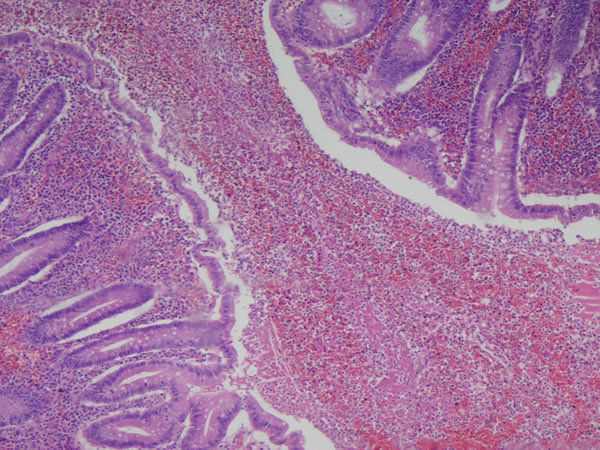

Image:

Intestino grosso - epitélio cilíndrico simples + epitélio secretor (células caliciformes) Neoplasia -adenocarcinoma de cólon Lado esquerdo: intestino normal Lado direito: Neoplasia |

Intestino grosso - Neoplasia - adenocarcinoma de cólon Note que as células neoplásicas não têm produção de muco. Epitélio pseudo-estratificadoe há aumento da relação núcleo/citoplasma e da densidade da cromatina |